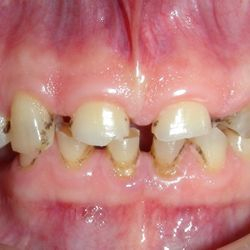

Ο 35χρονος αυτός ασθενής προσήλθε στο ιατρείο παραπονούμενος για το χρώμα και το σχήμα των άνω προσθίων δοντιών του καθώς και για το χρώμα των κάτω προσθίων δοντιών του.

Μετά από ένα βαθύ καθαρισμό των δοντιών, αποφασίστηκε να αποκατασταθούν τα άνω δόντια με νέες ολοκεραμικές όψεις και γέφυρες για σωστή απόδοση χρώματος και σχήματος.

Το χρώμα των κάτω δοντιών βελτιώθηκε μετά απο 3 συνεδρίες λεύκανσης στο ιατρείο.